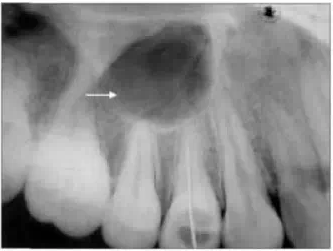

3.4 牙根吸收

牙齒根尖部分吸收在臨床上較為多見,在X線片上的影像表現(xiàn)也為大多數(shù)醫(yī)生所認(rèn)識;牙齒整個牙根的吸收在臨床較為少見,很多醫(yī)生不熟悉其在X線牙片上的表現(xiàn)。整個牙根吸收常發(fā)生在有外傷史的患牙。仔細(xì)觀察X線牙片,能隱約看到原有牙根的輪廓(圖5);如發(fā)生整個牙根吸收,該牙根不能被完整拔除,需作翻瓣手術(shù)去除。Laux等對常規(guī)根尖片表現(xiàn)與組織學(xué)檢查進(jìn)行比較,發(fā)現(xiàn)常規(guī)根尖片并不能夠準(zhǔn)確反映牙根吸收程度。X線水平及垂直方向上10°左右的改變也會對牙齒影像長度產(chǎn)生影響,所以拍攝牙片時最好采用平行定位投照根尖周片,將X線球管、目標(biāo)牙、膠片三者的位置關(guān)系保持恒定不變,從而有較精確的重復(fù)性和對照性。

有學(xué)者指出,牙根的吸收方向不同,在X線影像上的表現(xiàn)也不同;X線片在估計頰舌側(cè)牙根吸收方面不是很有效,但對估計近遠(yuǎn)中方向牙根吸收卻很有效。此外,數(shù)字化根尖片比普通根尖片能更精確地反映牙齒的實際長度。